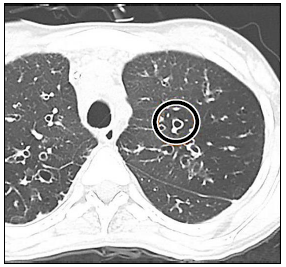

Observe o sinal encontrado em uma tomografia computadorizada:

Assinale a alternativa que apresenta corretamente o sinal, associando-o a uma patologia causadora.